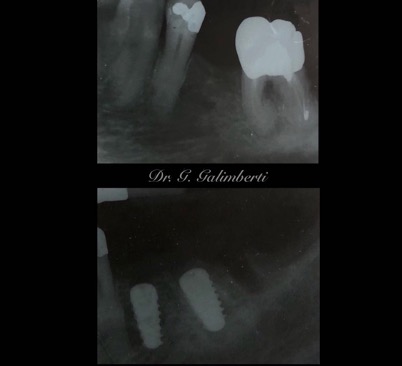

I primi impianti collocati dal Dott. Bruno Galimberti risalgono agli inizi degli anni 80 quanto ancora pochi in Italia praticavano l’implantologia. Dopo 40 anni molti di questi sono ancora tutt’oggi nella bocca dei pazienti.

Un impianto dentale o fixture è un corpo in titanio, totalmente biocompatibile, che viene posizionato nella mascella o mandibola con lo scopo di sostituire la radice di un dente naturale perso. Su di esso viene successivamente o immediatamente quando possibile (carico immediato) fissata la protesi ovvero la corona del dente restituendo funzione ed estetica.

Con l’implantologia oggi è possibile sostituire un solo dente come un’intera arcata anche in casi di deficit ossei grazie alla GBR (rigenerazione ossea guidata) che ci permette di intervenire quando la disponibilità ossea iniziale del paziente non sarebbe sufficiente.